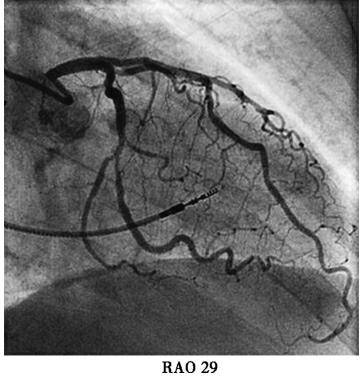

本例患者虽然有高血压、糖尿病等冠心病危险因素。起搏器电极植入后立刻发生的胸痛考虑与心绞痛关系不大,且患者未出现心电导联ST-T变化,胸痛原因主要考虑:起搏电极导致冠脉损伤?起搏电极刺破右室?遂台上决定立即行冠脉造影(图3);多个投照体位均可见起搏电极螺旋尖端触及前降支,因此决定行前降支血管内超声(IVUS)检查,结果于电极接触部位,血管8点钟方向可见强回声,距离血管外膜小于1mm;综合判断起搏电极损伤血管外膜导致胸痛的可能性大;随后进行电极重新植入,并再次造影排除起搏电极穿透冠脉可能,电极具体位置及冠脉造影见图4,心室起搏参数(阈值0.8V,阻抗670Ω,R波10.0mv)。患者症状完全消失,于导管室留观30分钟,复查心脏超声,心包内未见积液,排除起搏电极刺破右室可能,转回病房。

图4重新植入心室电极后冠脉造影